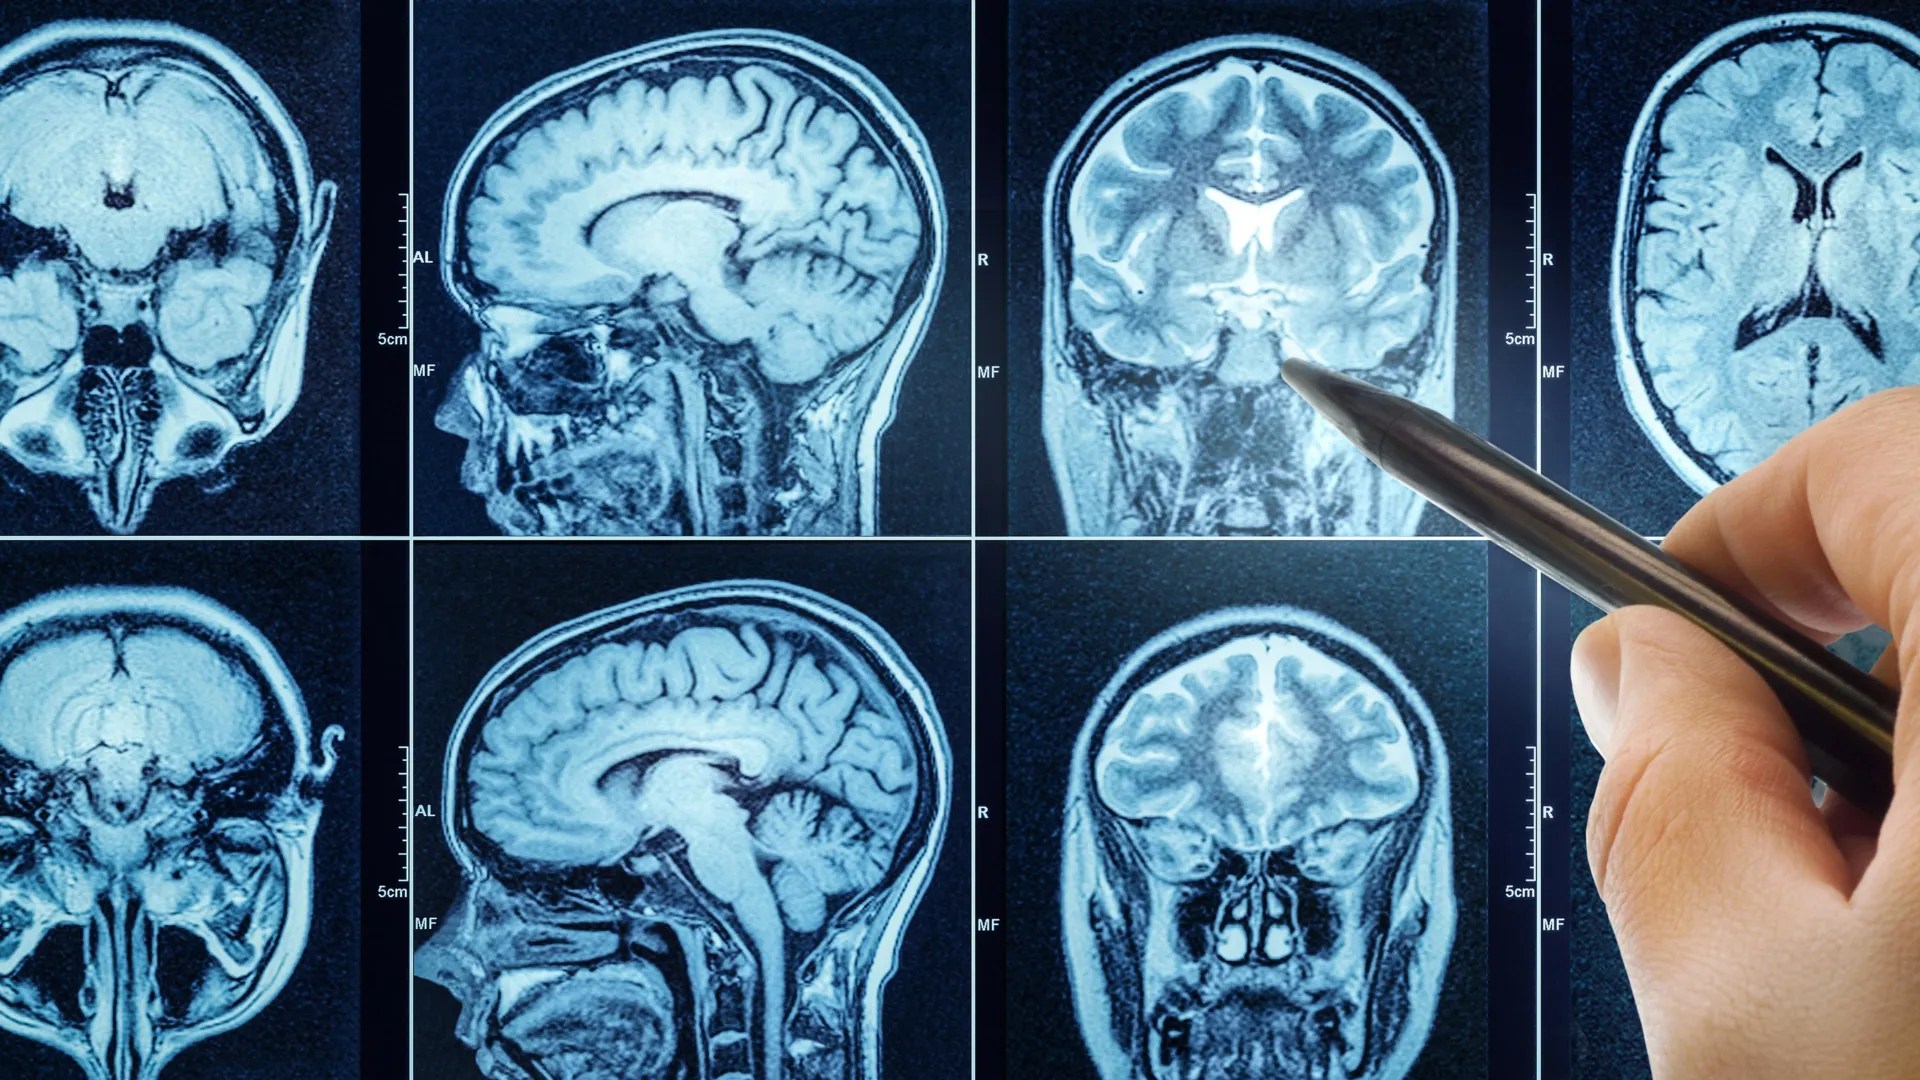

這項由Karolinska Institutet發表在eBioMedicine期刊上的研究,透過大腦影像分析,揭示了睡眠品質與大腦年齡之間的關聯性。對於長期關注認知老化與神經退化的台灣學者而言,這項研究不僅提供了新的研究方向,更突顯了改善睡眠對於維護大腦健康的潛在價值。

研究利用英國生物樣本庫(UK Biobank)中27,500名中年和老年人的數據,結合磁振造影(MRI)和機器學習技術,評估參與者的大腦生物年齡。研究發現,睡眠品質較差的個體,其大腦年齡平均比實際年齡高出一年。更具體地說,健康睡眠評分每降低一點,大腦年齡與實際年齡的差距就會擴大約六個月。這意味著,長期的睡眠不足或睡眠品質不佳,可能加速大腦的老化進程。